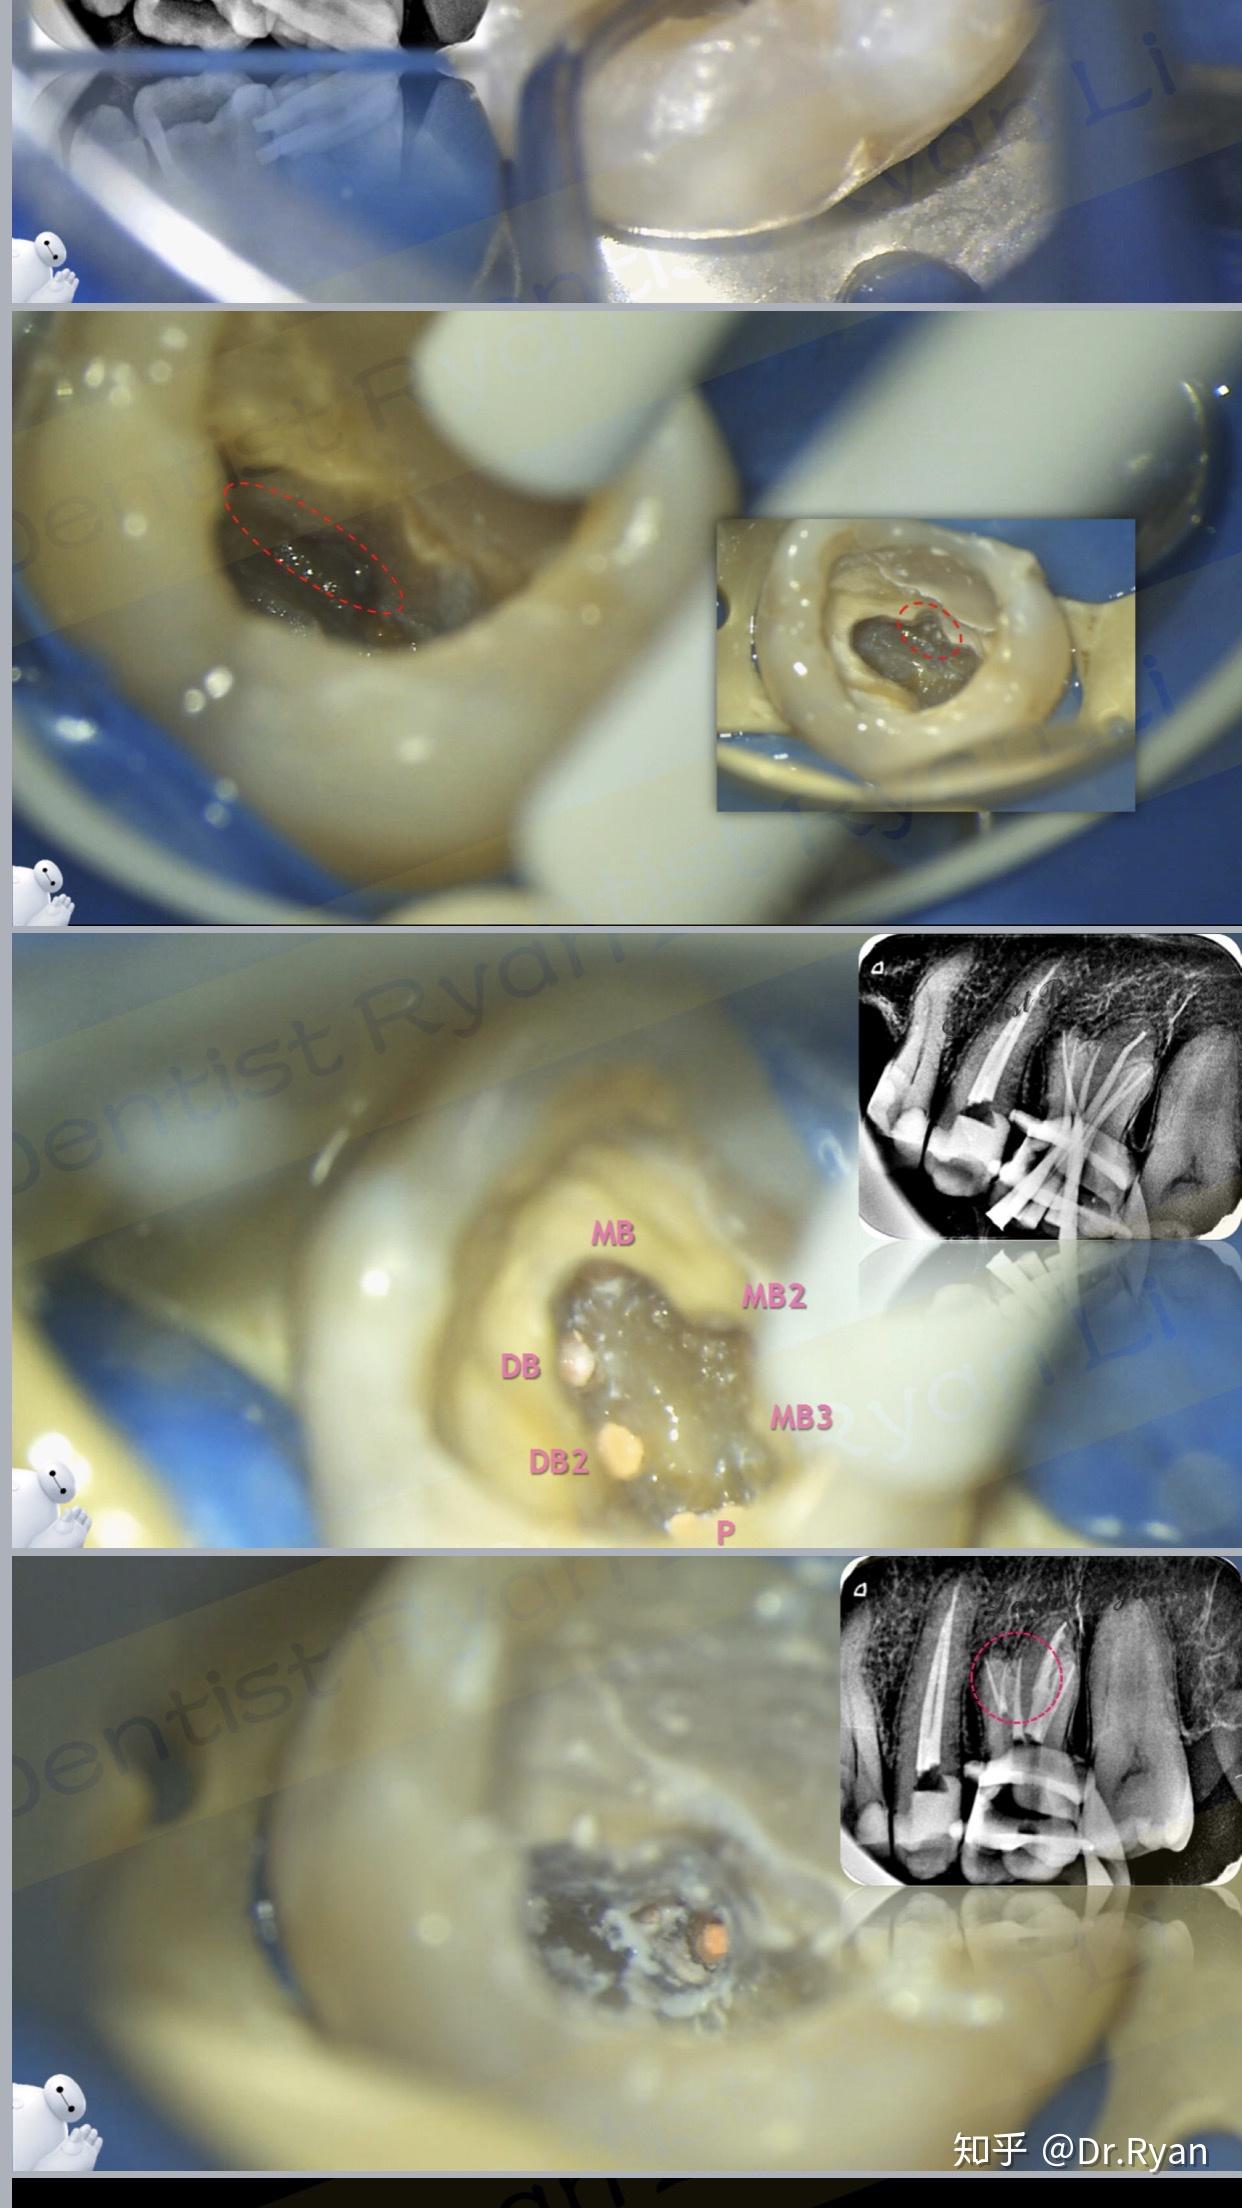

需要在一个耳机头上开个洞,然后在里面找到三四个牙根清理干净充填好

罕见的上下颌第一前磨牙牙根均为三根